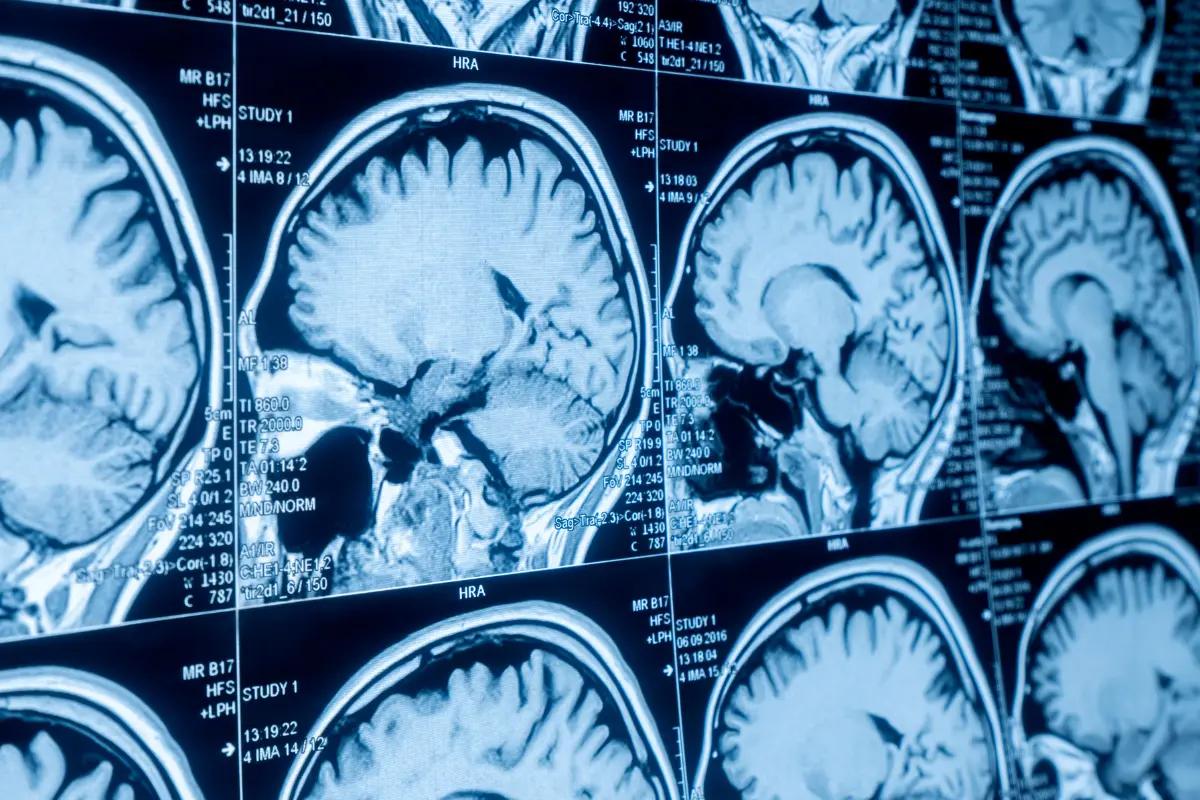

Brain injuries are not only among the most devastating physically, they also carry a huge economic impact for the victim. Information provided by The Brain Injury Institute reveals that medical treatment alone for even a “mild” injury to the brain (such as a minor concussion) can still be nearly $100,000, and that treating more serious brain injuries will cost a minimum of $3 million over the lifetime of the victim. Keep in mind that these are only the direct medical expenditures such as ER visits, provider co-pays, testing like X-rays and MRIs, and hospitalization. This doesn’t include any related costs the patient and their family will incur, which is often where the biggest financial impact is felt.